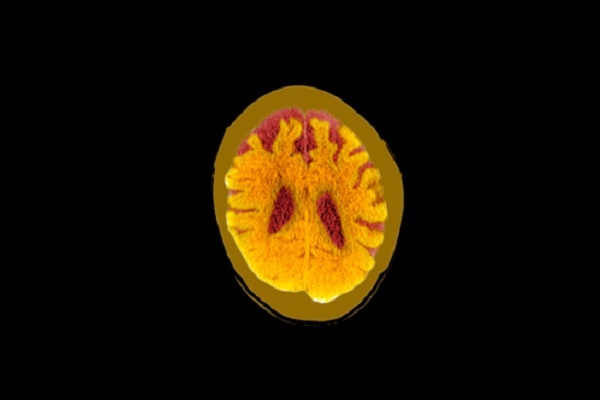

Một nghiên cứu mới cho thấy chấn động và chấn thương sọ não nói chung có thể ảnh hưởng lâu dài đến sức khỏe trí tuệ của con người.

Trong một nghiên cứu mới công bố trên tạp chí Alzheimer’s & Dementia dựa trên kho dữ liệu lớn theo dõi sức khỏe hàng chục ngàn người Mỹ suốt 25 năm qua, các tác giả nhận thấy, chấn thương sọ não, ngay cả những chấn thương nhẹ, có liên quan đến việc tăng nguy cơ sa sút trí tuệ về sau. Nghiên cứu cũng chỉ ra, những người bị chấn thương sọ não càng nhiều thì nguy cơ mắc chứng sa sút trí tuệ càng cao.

Khi các nhà nghiên cứu ở Đại học Pennsylvania phân tích dữ liệu về chấn thương sọ não, họ phát hiện, những người đã bị chấn thương sọ não một lần có nguy cơ mắc chứng sa sút trí tuệ cao hơn 25% so với những người không bị chấn thương. Nguy cơ đó tăng gấp đôi đối với những người bị chấn thương sọ não từ hai lần trở lên.